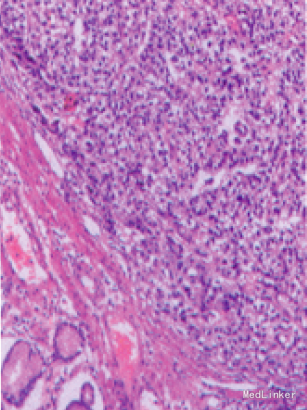

随访:患者出院后因终济原因,一直未进行化疗或放疗,3个月后复查:AFP83.08ng/ml,CEA 2.42ng/ml.但CT提示肝多发性转移瘤。现患者带瘤生存,精神和食欲尚可.一直服用中药治疗。 讨论:肝样腺癌有较特殊的病理学特征,组织学上主要由不同而又密切相关的腺癌区和肝样分化区两部分组成。腺癌区为管状腺癌或乳头状腺癌.而肝样区的瘤细胞特点和排列方式与肝癌相似,细胞大,多边形,胞浆丰富、嗜酸性,部分癌细胞胞浆透亮.核仁大而明显、位于细胞中央,癌细胞组成粱索状或实性窦状,其问被纤维血窦状问质分隔.两者之间有逐渐移行的过程。本病例可见到此病理表现。